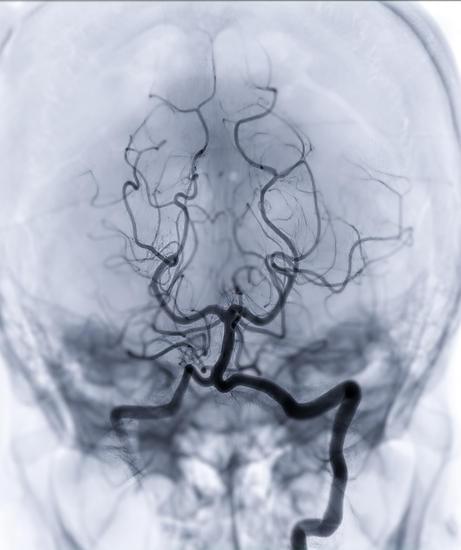

뇌혈관 조영술의 개요

뇌혈관 조영술(Cerebral Angiography)은 뇌의 혈관 상태를 자세히 검사하기 위한 의료 영상 진단 절차입니다.

이 검사는 뇌의 혈관에 염료(조영제)를 주입한 후 X-레이를 사용하여 혈관의 이미지를 얻습니다.

뇌혈관 조영술을 통해 뇌동맥류, 혈관 기형, 혈전, 혈관 폐쇄 또는 좁아짐과 같은 다양한 혈관 문제를 진단할 수 있습니다.